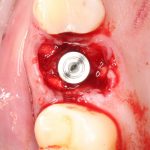

Я зафиксировал костный блок практически без адаптации на несколько винтов. Обрати внимание, что винты находятся в зоне, где не планируется установка имплантатов. Фиксация должна быть надежной, поскольку мне еще предстояла подготовка лунок для имплантатов. Трех винтов для этого вполне достаточно.

Дальнейшая адаптация костного блока свелась к сглаживанию острых краев. После чего я приступил к подготовке лунок и установке имплантатов.

Установка имплантатов.

Напомню, что для этой работы я выбрал субкрестальные имплантаты Ankylos C/X. Они прекрасно сочетаются с любым методом остеопластики.

Я не планирую установку супраструктур или коронок, поэтому на уровень первичной стабильности можно положить болт. Даже наоборот — чем меньше крутящий момент при установке, тем лучше. Для имплантатов Ankylos и подобных им, это особенно важно. В общем, момент силы при установке — не более 10-15 Нсм.

Ремарка: имплантаты с предустановленными имплантодержателями хороши тем, что с ними легко контролировать позиционирование имплантатов. В случае с Ankylos С/Х - еще и крутящий момент. Имплантодержатель должен отсоединяться от имплантата с легким щелчком. Если его клинит, и тебе приходится прикладывать для этого усилия, то ты, однозначно, превысил момент силы во время установки имплантата. Следовательно, жди проблем.

Глянем на то, что получилось:

Осталось адаптировать костный блок (убрать острые края), проверить его фиксацию и, при необходимости, добавить винты. Десятисекундное дело.